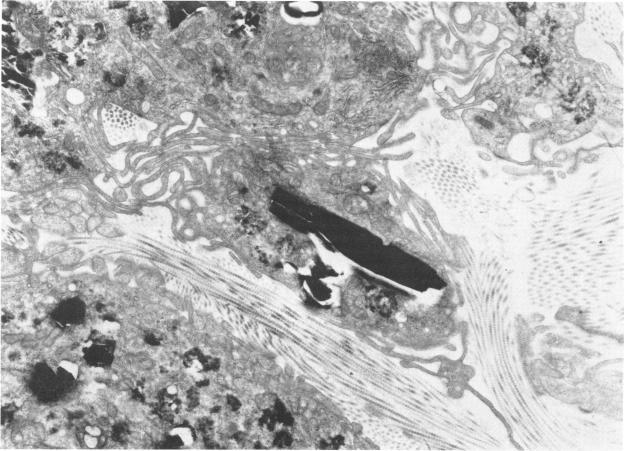

The pulmonary macrophage.

An overview of the pulmonary macrophage is provided, with particular emphasis on the origin of this cell and the adaptive mechanisms whereby the macrophagic system is able to respond to increased inhalant loads of organic and inorganic pollutants. Evidence is presented which favors an hematopoietic origin for the alveolar macrophage with a monocytic transportation compartment in the blood and an interstitial cell compartment in the lung in which cellular division and maturation may occur. Through the simple mechanism of increased cellular turnover this system of mononuclear phagocytes rapidly adapts to most inhalant challenges. In addition to its primary tasks phagocyte and destroyer of microorganisms the macrophage plays a pivotal role in the genesis of silicotic fibrosis, and it is possible that similar mechanisms may hold for a variety of cryptogenic fibroses. Paradoxically, destruction of collagen by the dual mechanisms of phagocytosis and the secretion of lytic enzymes may also occur. The relevance of this secretory function of the macrophage to the pathogenesis of destructive diseases of the lung such as emphysema remains to be determined.